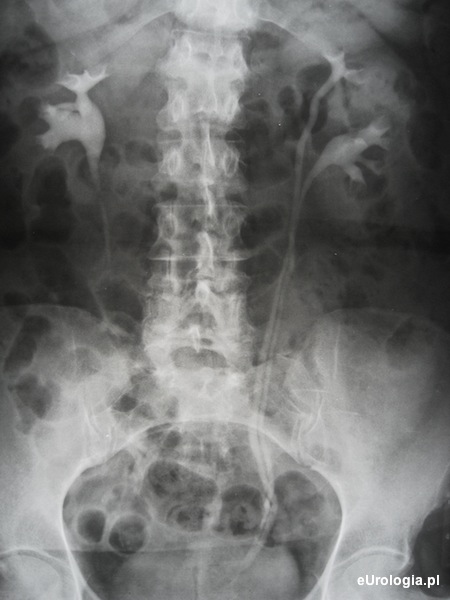

Fot. Moczowód podwójny - obraz urograficzny. W cystoskopii widoczne dwa oddzielne ujścia lewych moczowodów.